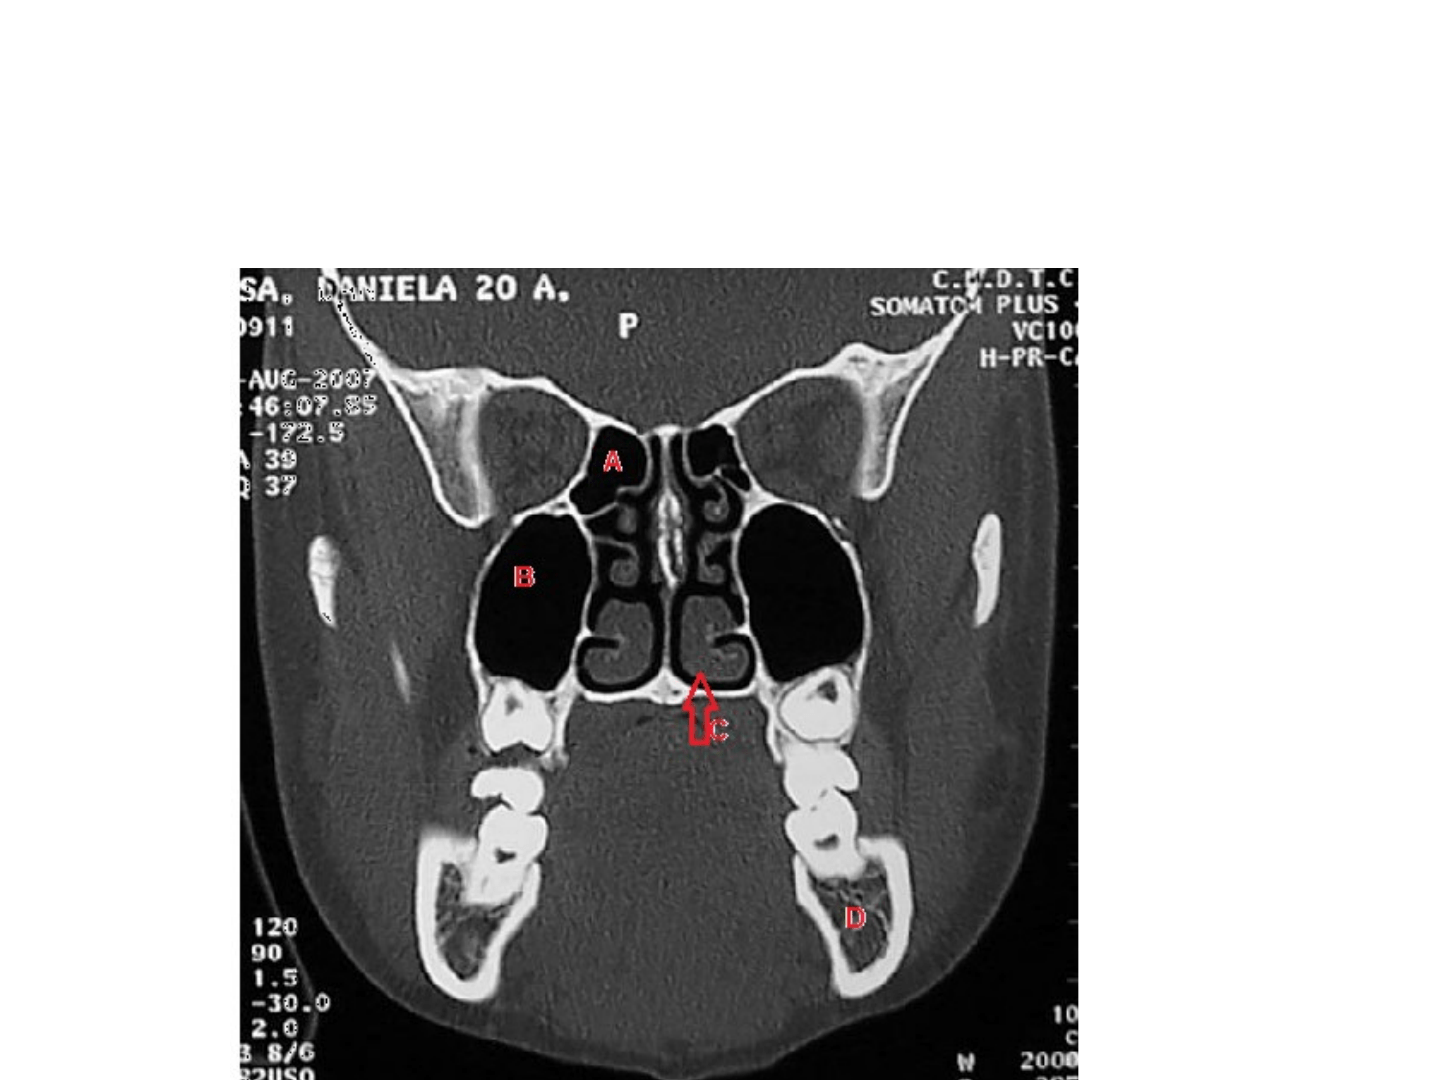

•

A: Celdilla E

tmoidal

B: Seno Ma

xilar

C: Corne

t

e in

f

erior

D: Ma

xilar in

erior (mandíbula)